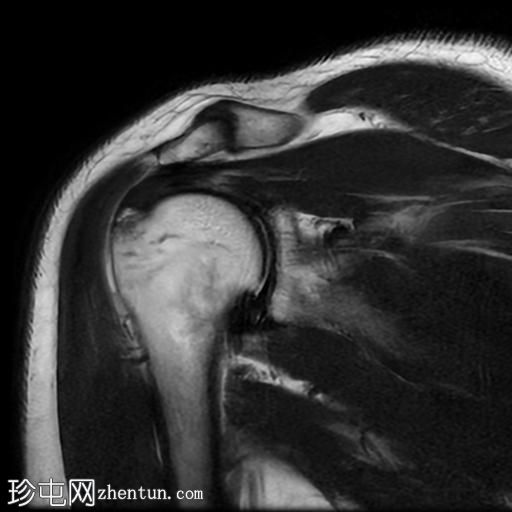

冠状位PD序列

脂肪抑制序列

冈上肌腱关节面中前部纤维可见部分撕裂(边缘撕裂),伴局部骨髓水肿。

冈上肌腱关键区纤维以及冈下肌腱均可见肌腱病。

肩锁关节周围可见轻度关节囊肥厚和退行性改变。

此外,肩峰下滑囊内可见积液。

MRI 检查结果符合冈上肌腱的典型边缘撕裂,也称为部分关节面肌腱撕脱。